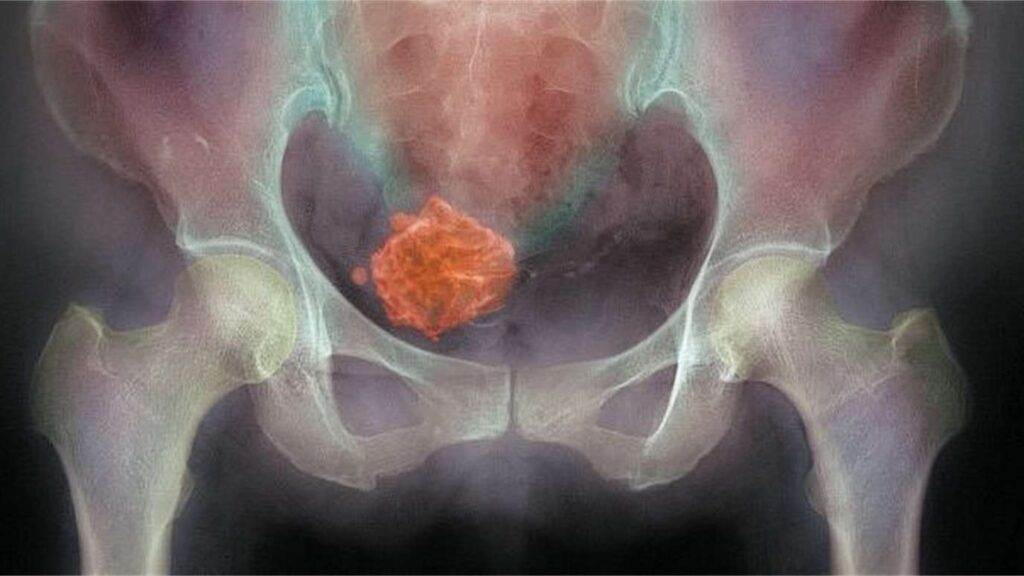

„Máte myom.“

Dvě slova. A svět se zastavil.

Něco tam roste. Něco, co tam nemá být. Něco cizího.

Cítila jsem se obsazená. Jako by se do mého těla nastěhoval někdo, koho jsem nezvala.